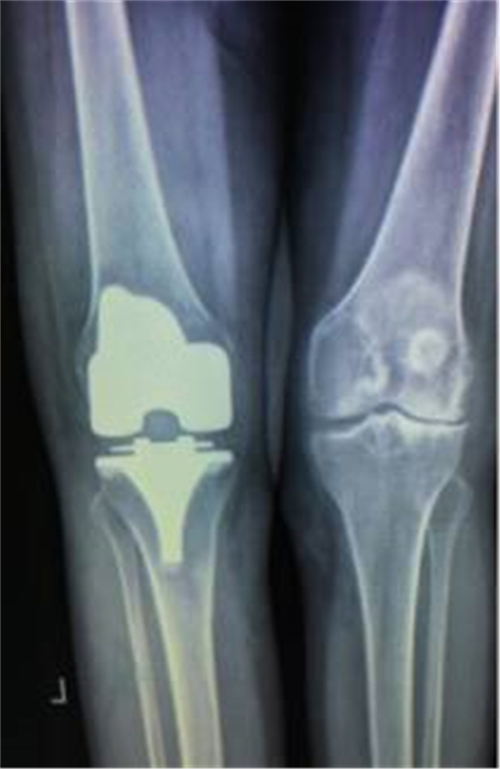

术后X线